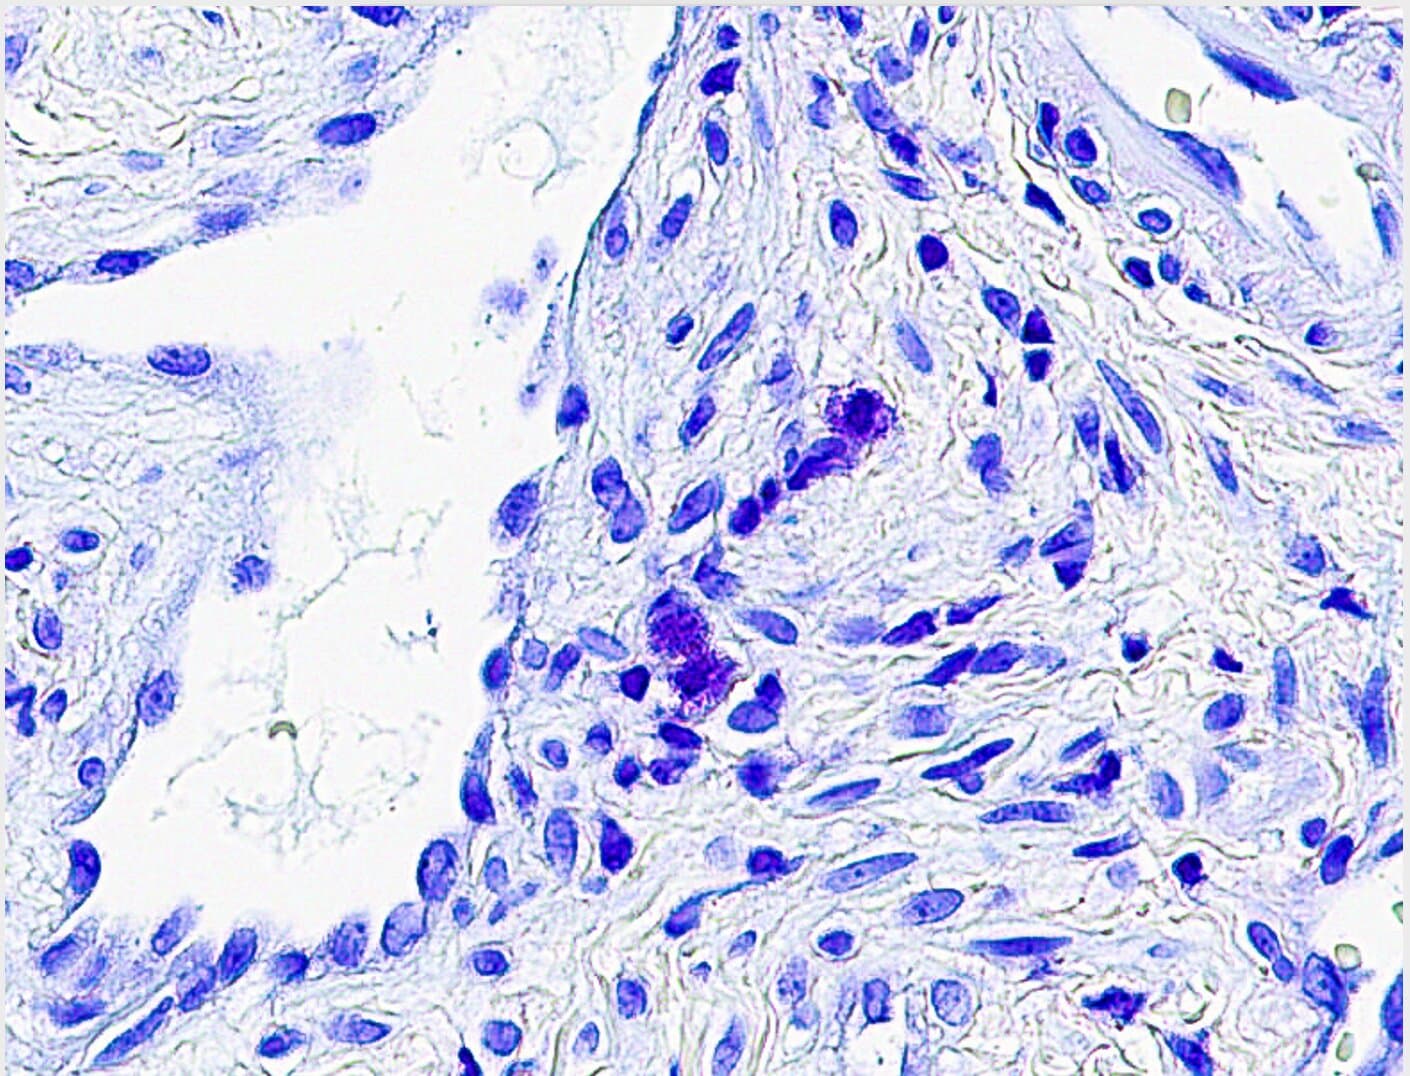

The collaborative research team identified specific biological markers and inflammatory patterns that differentiate toxin-induced chronic rhinosinusitis from other presentations of this widespread condition. Rather than displaying the typical characteristics commonly observed in standard CRS cases, veterans with exposure histories to military burn pits and similar airborne hazards exhibited a distinct disease profile. This distinction carries significant implications for how clinicians approach diagnosis, treatment, and long-term management strategies for affected service members.

The UC San Diego and VA San Diego research team examined how these specific environmental exposures interact with the respiratory epithelium and immune system. Rather than causing the generalized inflammation typically associated with conventional CRS, the toxin exposure pattern appears to activate a distinctive inflammatory cascade. This specialized immune response may explain why standard treatment approaches sometimes prove less effective for this veteran population compared to other CRS patients.